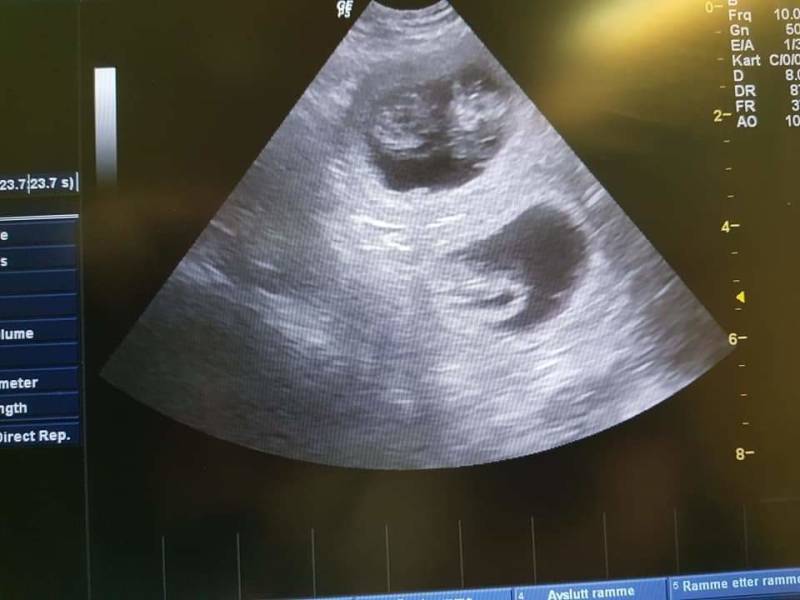

12-02-2021

Er zijn 6/7 vruchtjes gezien.